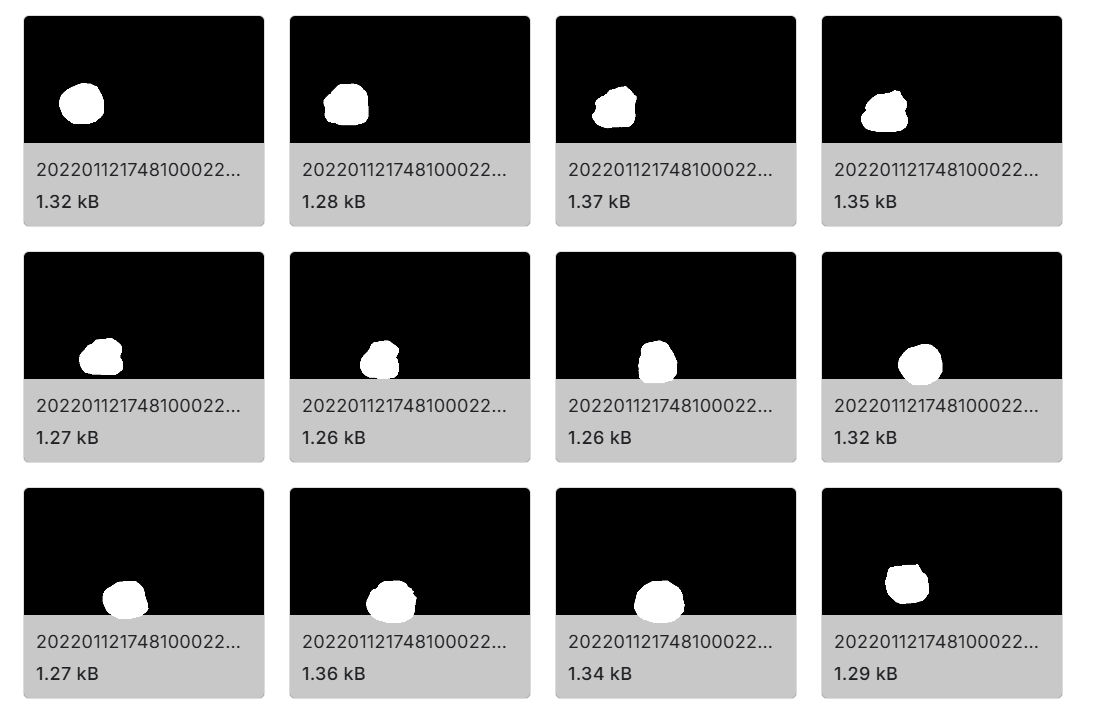

- Mask图像 :由技术人员创建并经专家验证的相应蒙版图像,共 1100 张图像。这些蒙版对于颈动脉分割非常有价值。

- 颈动脉分割 :通过对颈动脉的分割,可以更清晰地观察和分析颈动脉的结构和病变情况,为疾病的诊断和治疗提供依据。